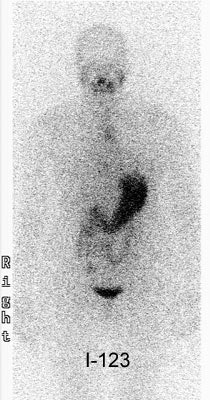

![]() |

| Diagnostic anterior whole-body images taken with 131I, left, and 123I, right, of a 50-year-old male who was evaluated for sites of recurrent, differentiated thyroid cancer after 131I ablation. The body outline is easily identified in the 123I scan. Image courtesy of Dr. Stephen Gerard. |